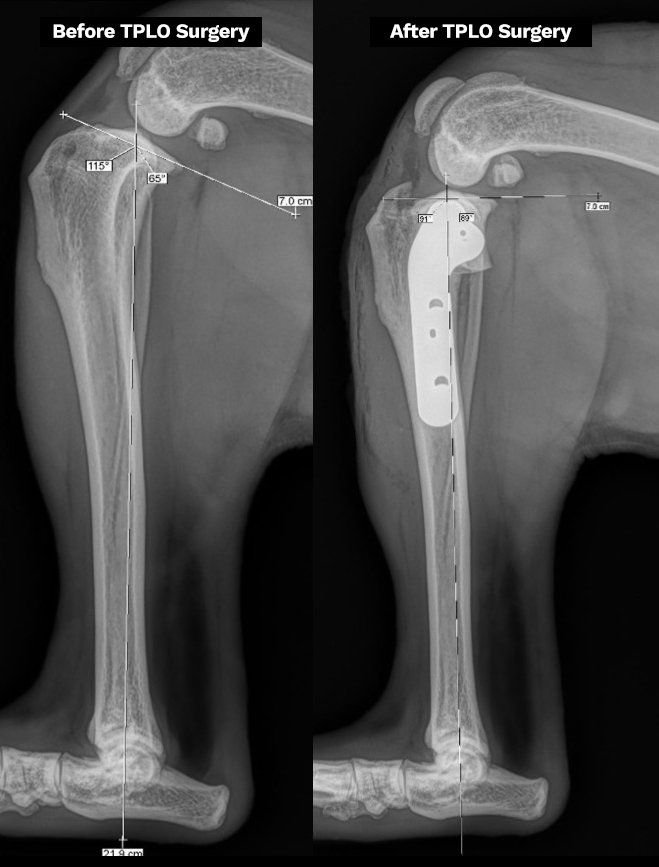

Q: What is the TPLO Procedure?

A: Tibial Plateau Leveling Osteotomy (TPLO) is a surgical procedure designed to stabilize the knee after a cranial cruciate ligament (CCL) tear in dogs.

In a normal knee, the top of the tibia (shin bone) slopes backward, allowing the femur (thigh bone) to slide down this slope. When the CCL tears, this sliding motion causes pain, instability, and joint damage.

How TPLO Works:

The tibial slope is surgically altered to remove the backward slant. Learn how TPLO surgery works.

This prevents abnormal movement, eliminating the need for the damaged ligament.

The quadriceps muscle takes over knee stabilization, allowing for natural movement and weight-bearing.

TPLO surgery is the gold standard for active and large-breed dogs, offering long-term joint stability, faster recovery, and a reduced risk of arthritis compared to other procedures.

Excessive Tibial Plateau Angle (TPA) – Though linked to ligament stress, research shows it alone does not cause rupture. Learn more about TPA on the X-Ray.